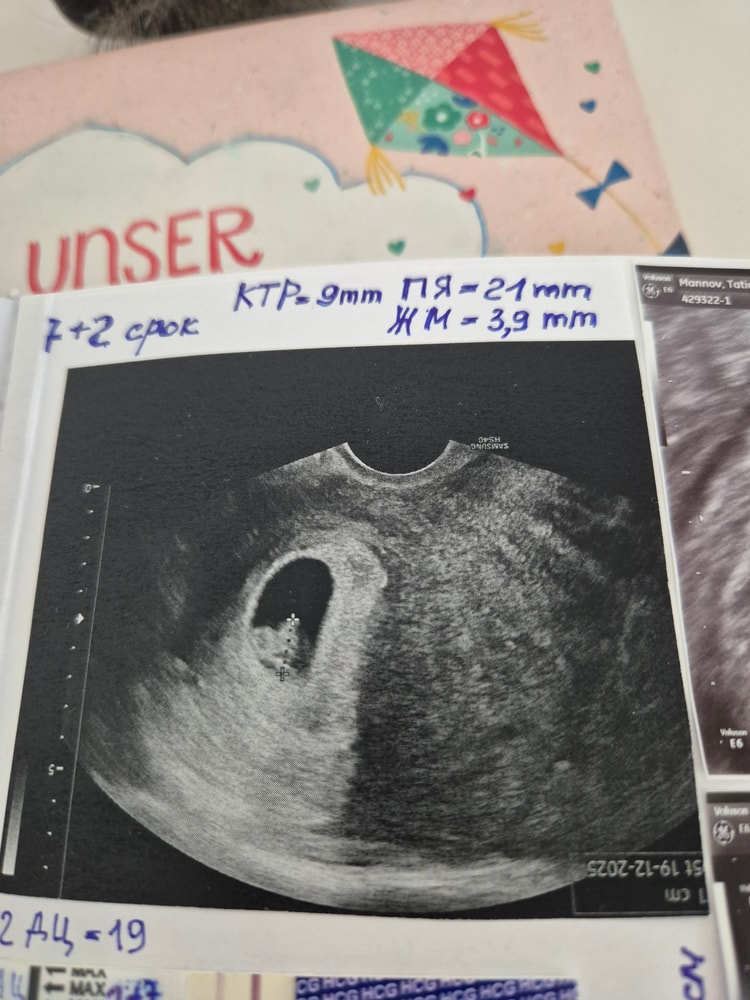

Татьяна, могу свою историю рассказать. Я пришла на узи на сроке 6+1( но у меня О была на 20 дц, это я знаю) и на узи было только ПЯ. Я врача сразу предупредила на счёт О, она у меня от срока отняла эту разницу и получился срок 5+2. Затем я пришла в 7+2 было уже СБ, а по старому сроку это было 8+1.

Таня, это моё узи на сроке 7+1. У меня вроде все по нормам, а у вас ктр невелик, жм большое, я понимаю что есть погрешности, но может узист рукожопый, хз. И получается за 5 дней ПЯ совсем не выросло, но эмбрион появился.

Таня, фото нет , написана : пя 11 мм , жм 6,4 мм , ктр 3,8 мм , сердцебиение не определяется

И в заключении написала : признаки неразвивающейся маточной беременности 7/5 недель